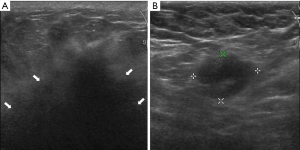

In our study, the maximum size of breast lesions in 6 cases ranged from 1.2 to 4.5 cm, and 1 case with a diffused breast lesion was identified (Figure 1). The shape of breast metastases in 5 (5/7, 71.4%) cases was irregular, with the other 2 (2/7, 28.6%) cases having an oval shape (Figure 2). The margin of metastases in 6 (6/7, 85.7%) cases was indistinct, while in the remaining case the margin was noted to be well circumscribed. The lesions were hypoechoic in all cases (7/7, 100.0%) and had heterogeneous internal echogenicity in 5 (5/7, 71.4%) cases, while homogeneous internal echogenicity was found in 2 (28.6%) cases. The lesion orientation of 6 (6/7, 85.7%) cases was parallel (wider than tall), 3 (3/7, 42.9%) cases showed enhancement posterior feature (Figure 3), and 1 (1/7, 14.3%) case had a feature of posterior acoustic shadowing. Microcalcification was not observed in any patient. Color Doppler US detected blood flow in 2 (2/7, 28.6%) cases. Associated secondary signs, including edema and skin thickening, were found in 5 (5/7, 71.4%) cases. The final BI-RADS assessment categories were BI-RADS 3 in 1 (1/7, 14.3%) case, BI-RADS 4A in 1 (1/7, 14.3%) case, BI-RADS 4B in 1 (1/7, 14.3%) case, BI-RADS 4C in 3 (3/7, 42.9%) cases, BI-RADS 5 in 1 (1/7, 14.3%) case.

The common US features of primary breast cancer are irregular, not parallel, indistinct, irregular, hypoechoic, homogeneous masses with microcalcification and posterior acoustic shadowing (19). The common US features of breast metastases from lung cancer are nodules that are irregular, indistinct, hypoechoic, and parallel masses without calcification. The maximum size of breast metastases from lung adenocarcinoma was larger than that of large cell and small cell lung cancer. In addition, internal echogenicity was homogeneous in patients with large cell and small cell lung cancer, while it was heterogenous in patients with adenocarcinoma. Most lesions were parallel to the skin. Posterior acoustic enhancement was also observed in our study. This is different from the US feature of primary breast cancer, where posterior acoustic shadowing is most typical (20). However, we still observed 1 patient with a diffused breast metastasis featuring posterior acoustic shadowing, which, to our knowledge, is the first report of these features in breast metastases. Calcification, which is rarely observed in metastasis to the breast, may be helpful in distinguishing stage IV disease from a primary breast cancer. Only 1 prior study has reported a case of calcifications in lung cancer metastatic to the breast (13). Color blood flow signal was detected in 2 patients, which is different from the abundant vascularity of primary breast carcinoma (21). Sippo et al. (20) and Moreno-Astudillo et al. (22) reported that the US manifestation of other cancer metastases to the breast were round or oval hypoechoic lesions, which could be diagnosed as benign nodules. This study also observed a case of metastatic small cell lung cancer to the breast, which demonstrated an oval shape and indistinct margin, and homogeneous internal echogenicity. In contrast, Luh et al. (23) reported 2 small lung cancer masses with a distinct margin and heterogeneous internal echogenicity.